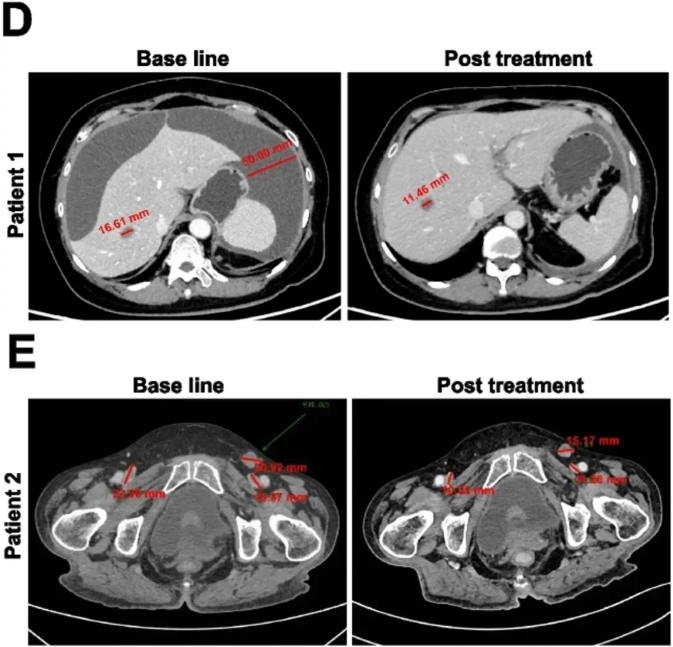

值得一提的是,其中2例患者的疗效尤为亮眼:其中患者1肝转移灶缩小31%,腹腔积液完全消失(详见下图D);患者2可测量病灶总最大直径缩小42%(详见下图E)。

▲图源“BMC”,版权归原作者所有,如无意中侵犯了知识产权,请联系我们删除